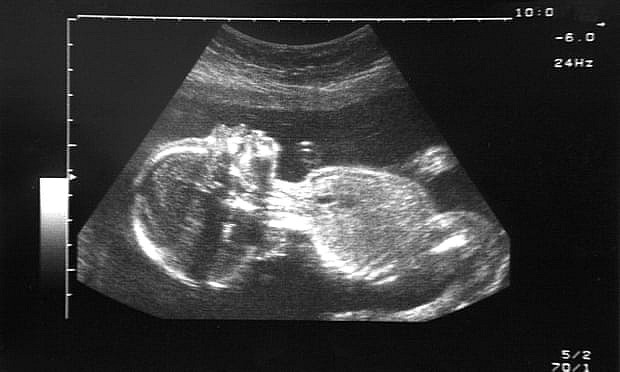

Trong những năm gần đây, sau nhiều cuộc nghiên cứu, các nhà khoa học đã sửng sốt phát hiện ra  việc tiếp xúc với ô nhiễm không khí có thể có tác động tiêu cực đến thai nhi đang phát triển trong bụng mẹ, dẫn đến cân nặng khi sinh thấp hơn bình thường hoặc bị sinh non. Nhưng họ không tìm được bằng chứng,  cho đến tận bây giờ, mọi thứ đã sáng tỏ.

Một nhóm các nhà khoa học ở nước Bỉ đã tìm thấy hàng chục nghìn hạt gây ô nhiễm không khí trong nhau thai – vốn được coi là hàng rào tự nhiên che chở các thai nhi đang còn nằm yên trong bụng mẹ. Điều này cho thấy từ khi chưa ra đời, trẻ đã bị ảnh hưởng trực tiếp bởi carbon đen đến từ các loại khí thải do đốt nhiên liệu. Nghiên cứu này ngay lập tức được công bố trên Tạp chí Nature Communications.

Cụ thể, trong mỗi mẫu nhau thai được phân tích, các chuyên gia tìm thấy tới hàng chục nghìn hạt bụi nhỏ trên mỗi milimet vuông mô. Những hạt này xâm nhập vào nhau thai thông qua hoạt động hít thở của mẹ bầu. Từ đó gây nên các vấn đề nghiêm trọng như sinh non, trẻ thiếu cân và làm tăng khả năng sảy thai, thai lưu. Kết quả nghiên cứu cho thấy, chính độc tố trong các hạt ô nhiễm này là nguyên nhân gây tổn thương cho cả bà mẹ và em bé, không chỉ là phản ứng viêm do ô nhiễm thông thường.

Tác giả của công trình nghiên cứu - Hannelore Bové, nhà nghiên cứu sau tiến sĩ tại Trung tâm Khoa học Môi trường thuộc Đại học Hasselt, cho biết: “Hầu hết các nghiên cứu đã được thực hiện là nghiên cứu dịch tễ học. Bây giờ chúng tôi có một phép đo trực tiếp về tác động của các hạt carbon đen không dựa trên mô hình mà dựa trên các phép đo ở thai nhi, nhau thai”.

Còn trong nhau thai, carbon đen có thể gây viêm, dẫn đến các vấn đề sức khỏe khác vô cùng nguy hiểm. Các nhà khoa học phát hiện ra rằng, những bà mẹ càng tiếp xúc với không khí bị ô nhiễm trong tần suất nhiều thì càng có nhiều carbon đen xâm chiếm nhau thai.

Các nhà khoa học đã kiểm tra nhau thai của 20 phụ nữ ở Bỉ, thực hiện sinh thiết ở cả hai: mẹ và thai nhi ngay sau khi sinh. Những người phụ nữ được chọn dựa trên nơi mà họ sống: 10 người sống ở những nơi họ tiếp xúc với lượng carbon đen tương đối cao, 10 người sống ở những được coi là có mức phơi nhiễm thấp. Các nhà khoa học cũng đã xem xét 5 vị trí của nhau thai từ sảy thai xảy ra trong khoảng từ 12-31 tuần của thai kỳ.

Kết quả, số lượng hạt gây ô nhiễm phát hiện trong nhau thai có sự tương quan khá mật thiết với điều kiện sống của người mẹ: Có trung bình 20.000 hạt nano ô nhiễm trên mỗi milimet khối mô nhau thai của những thai phụ sống gần đường lớn. Con số này đối với những người sống xa đường lớn là trung bình 10.000 hạt/milimet khối mô. Các chuyên gia còn phân tích mẫu nhau thai của các thai bị sảy và tìm thấy các hạt ô nhiễm trong bào thai 12 tuần tuổi.

Trong y học, nhau thai đóng một vai trò quan trọng trong thai kỳ. Nó cung cấp một “hàng rào tự nhiên” giữa mẹ và thai nhi và cung cấp oxy cũng như chất dinh dưỡng cho em bé đang phát triển. Một nghiên cứu trước đó, chưa được công bố đã được trình bày tại Hội nghị quốc tế của Hiệp hội Hô hấp châu Âu đưa ra dấu hiệu đầu tiên rằng carbon đen có mặt trong nhau thai. Trong công trình đó, các nhà nghiên cứu từ Đại học Queen Mary ở Luân Đôn đã tìm thấy carbon đen trong các tế bào từ 5 vị trí của nhau thai. Tuy nhiên, vì các tế bào đã được loại bỏ khỏi nhau thai, nên không rõ liệu chúng đến từ phía mẹ hay do thai nhi sinh ra bị phơi nhiễm.